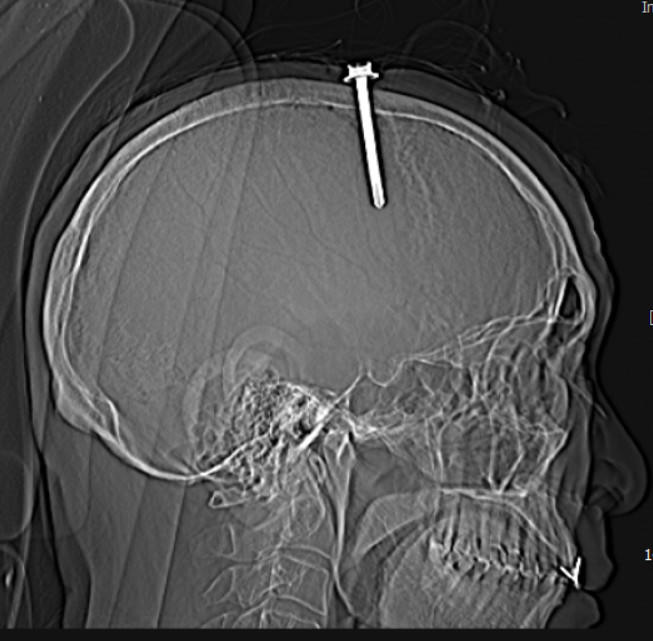

Tại bệnh viện, kết quả khám lâm sàng và chụp cắt lớp vi tính sọ não cho thấy bệnh nhân có vết thương sọ não, vết thương xoang tĩnh mạch dọc trên do dị vật kim loại cắm vào vùng đỉnh bên trái, cạnh xoang tĩnh mạch dọc trên. Dị vật có đường kính 0.5 cm, chiều dài 5,1cm.

Hình ảnh cây đinh trên phim chụp cắt lớp sọ não. Ảnh: BVĐK tỉnh Thanh Hóa. |